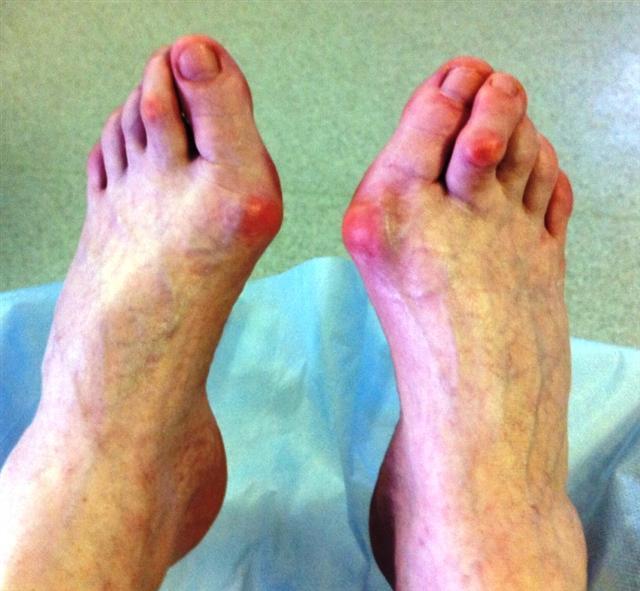

Если Вы посетители эту страницу нашего сайта, значит, у Вас есть проблемы со стопами. Наиболее частой патологией стопы, с которой пациенты обращаются к ортопеду является деформация переднего отдела стопы (поперечное плоскостопие с вальгусной деформацией первого пальца ( шишки или косточки в области первого пальца).

Данное заболевание возникает у лиц молодого возраста и характеризуется прогрессирующим течением. Распластанность переднего отдела стопы с вальгусной деформацией первого пальца сопровождается болевым синдромом, нарушает опорную функцию конечности, затрудняет пользование стандартной обувью, а в тяжёлых случаях приводит к снижению трудоспособности и нарушению социальной адаптации.

Чаще всего вальгусная деформация большого пальца стопы (hallux valgus) встречается у женщин. Согласно статистике на одного мужчину, страдающего этим заболеванием, приходится десять женщин. Это может быть связано с генетической или анатомической предрасположенностью женщин к развитию данного состояния. Но основой причиной такой «половой дифференцировки» этой патологии, является стиль обуви, который присущ женщинам – узкие носки и высокие каблуки.